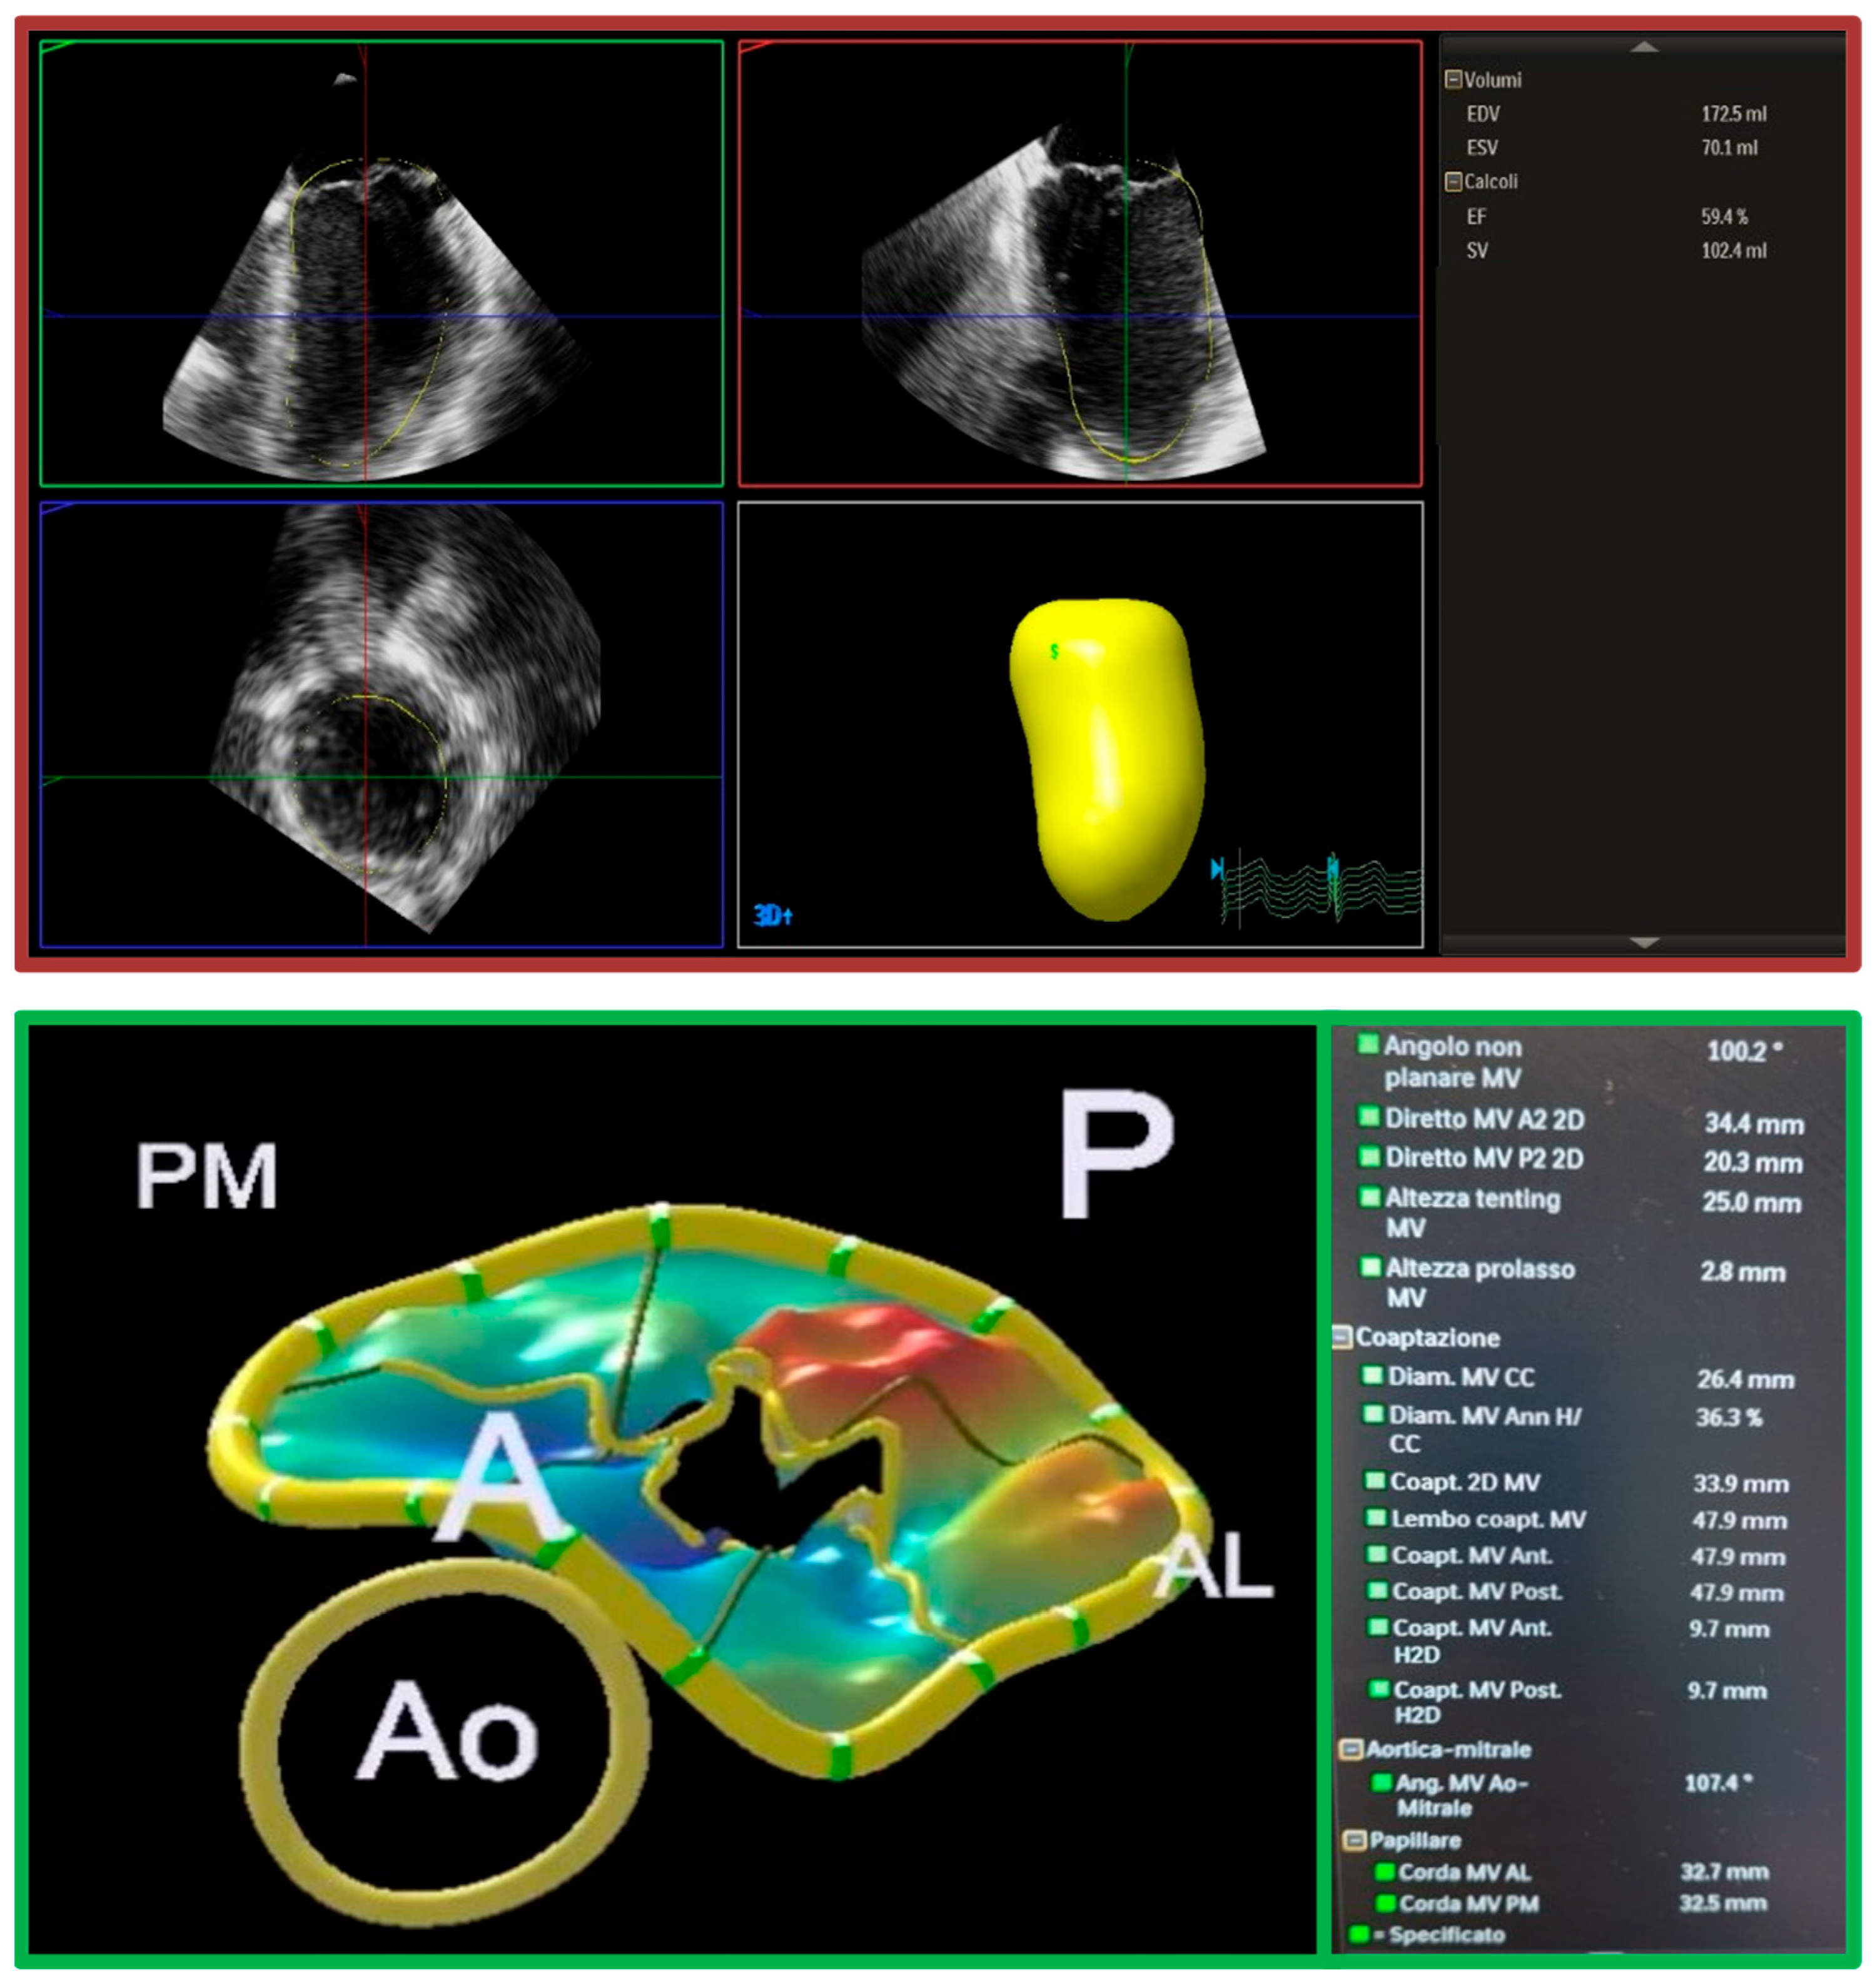

- Levy, F.; Marechaux, S.; Iacuzio, L.; Schouver, E.D.; Castel, A.L.; Toledano, M.; Rusek, S.; Dor, V.; Tribouilloy, C.; Dreyfus, G. Quantitative assessment of primary mitral regurgitation using left ventricular volumes obtained with new automated three-dimensional transthoracic echocardiographic software: A comparison with 3-Tesla cardiac magnetic resonance. Arch. Cardiovasc. Dis. 2018, 111, 507–517. [Google Scholar] [CrossRef]

- Marechaux, S.; Le Goffic, C.; Ennezat, P.V.; Semichon, M.; Castel, A.L.; Delelis, F.; Lemahieu, J.M.; Menet, A.; Graux, P.; Tribouilloy, C. Quantitative assessment of primary mitral regurgitation using left ventricular volumes: A three-dimensional transthoracic echocardiographic pilot study. Eur. Heart J. Cardiovasc. Imaging 2014, 15, 1133–1139. [Google Scholar]

- Marsan, N.A.; Westenberg, J.J.M.; Ypenburg, C.; Delgado, V.; van Bommel, R.J.; Roes, S.D.; Nucifora, G.; van der Geest, R.J.; de Roos, A.; Reiber, J.C.; et al. Quantification of Functional Mitral Regurgitation by Real-Time 3D Echocardiography. JACC Cardiovasc. Imaging 2009, 2, 1245–1252. [Google Scholar] [CrossRef]